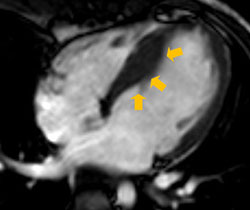

• 図3:遅延造影MRI (短軸):心サルコイドーシスの症例

心室中隔に遅延造影を認める

(黄色矢印部位の高信号領域・白色部位)。

同部位の心筋のダメージの範囲を評価できる。